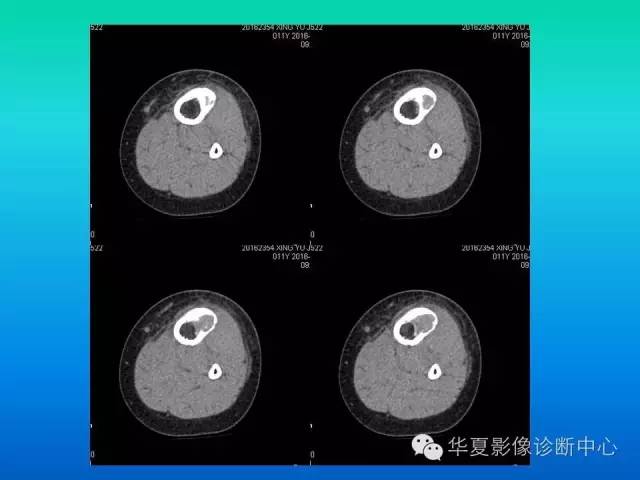

• 【病例】耻骨黏液型软骨肉瘤1例X线CT影像表现

【病例】耻骨黏液型软骨肉瘤1例X线CT影像表现